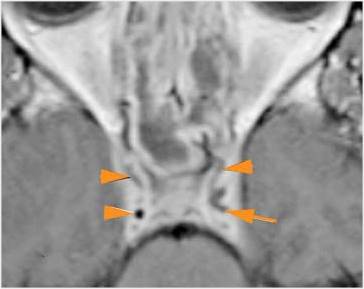

There is evidence of thrombus, thrombophlebitis or other occlusive or inflammatory process of the cavernous sinus.